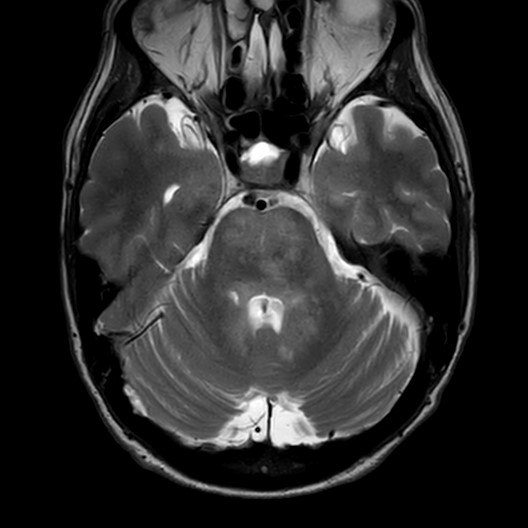

Axial T2 weighted MRI.jpg